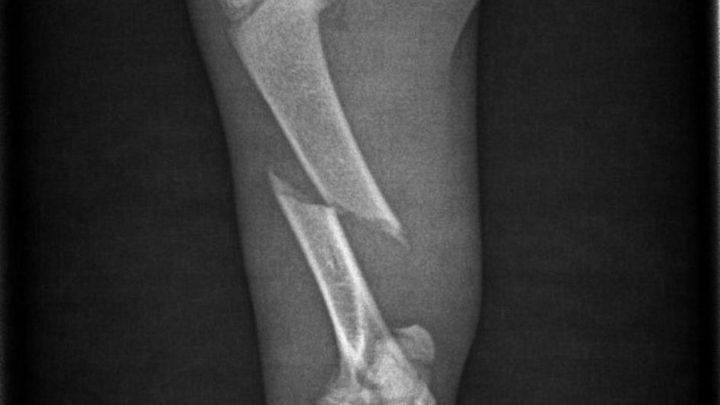

Nach längeren Warten, bekam ich dann die Nachricht mit dem Röntgenbild, wo man deutlich sehen kann das es ein bruch ist und Operiert werden muss.